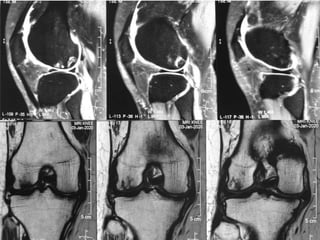

The document presents a detailed case study of a patient with transient osteoporosis of the hip (TOH) and spontaneous osteonecrosis of the knee (SONK) treated at Choithram Hospital & Research Centre in India. Over 20 years, the patient experienced multiple episodes of TOH and SONK with no history of trauma or co-morbidities, resulting in resolutions and recurrences of conditions. The information is intended for orthopedic surgery students and highlights personal experiences and case collections, with a disclaimer regarding content usage and potential controversies.